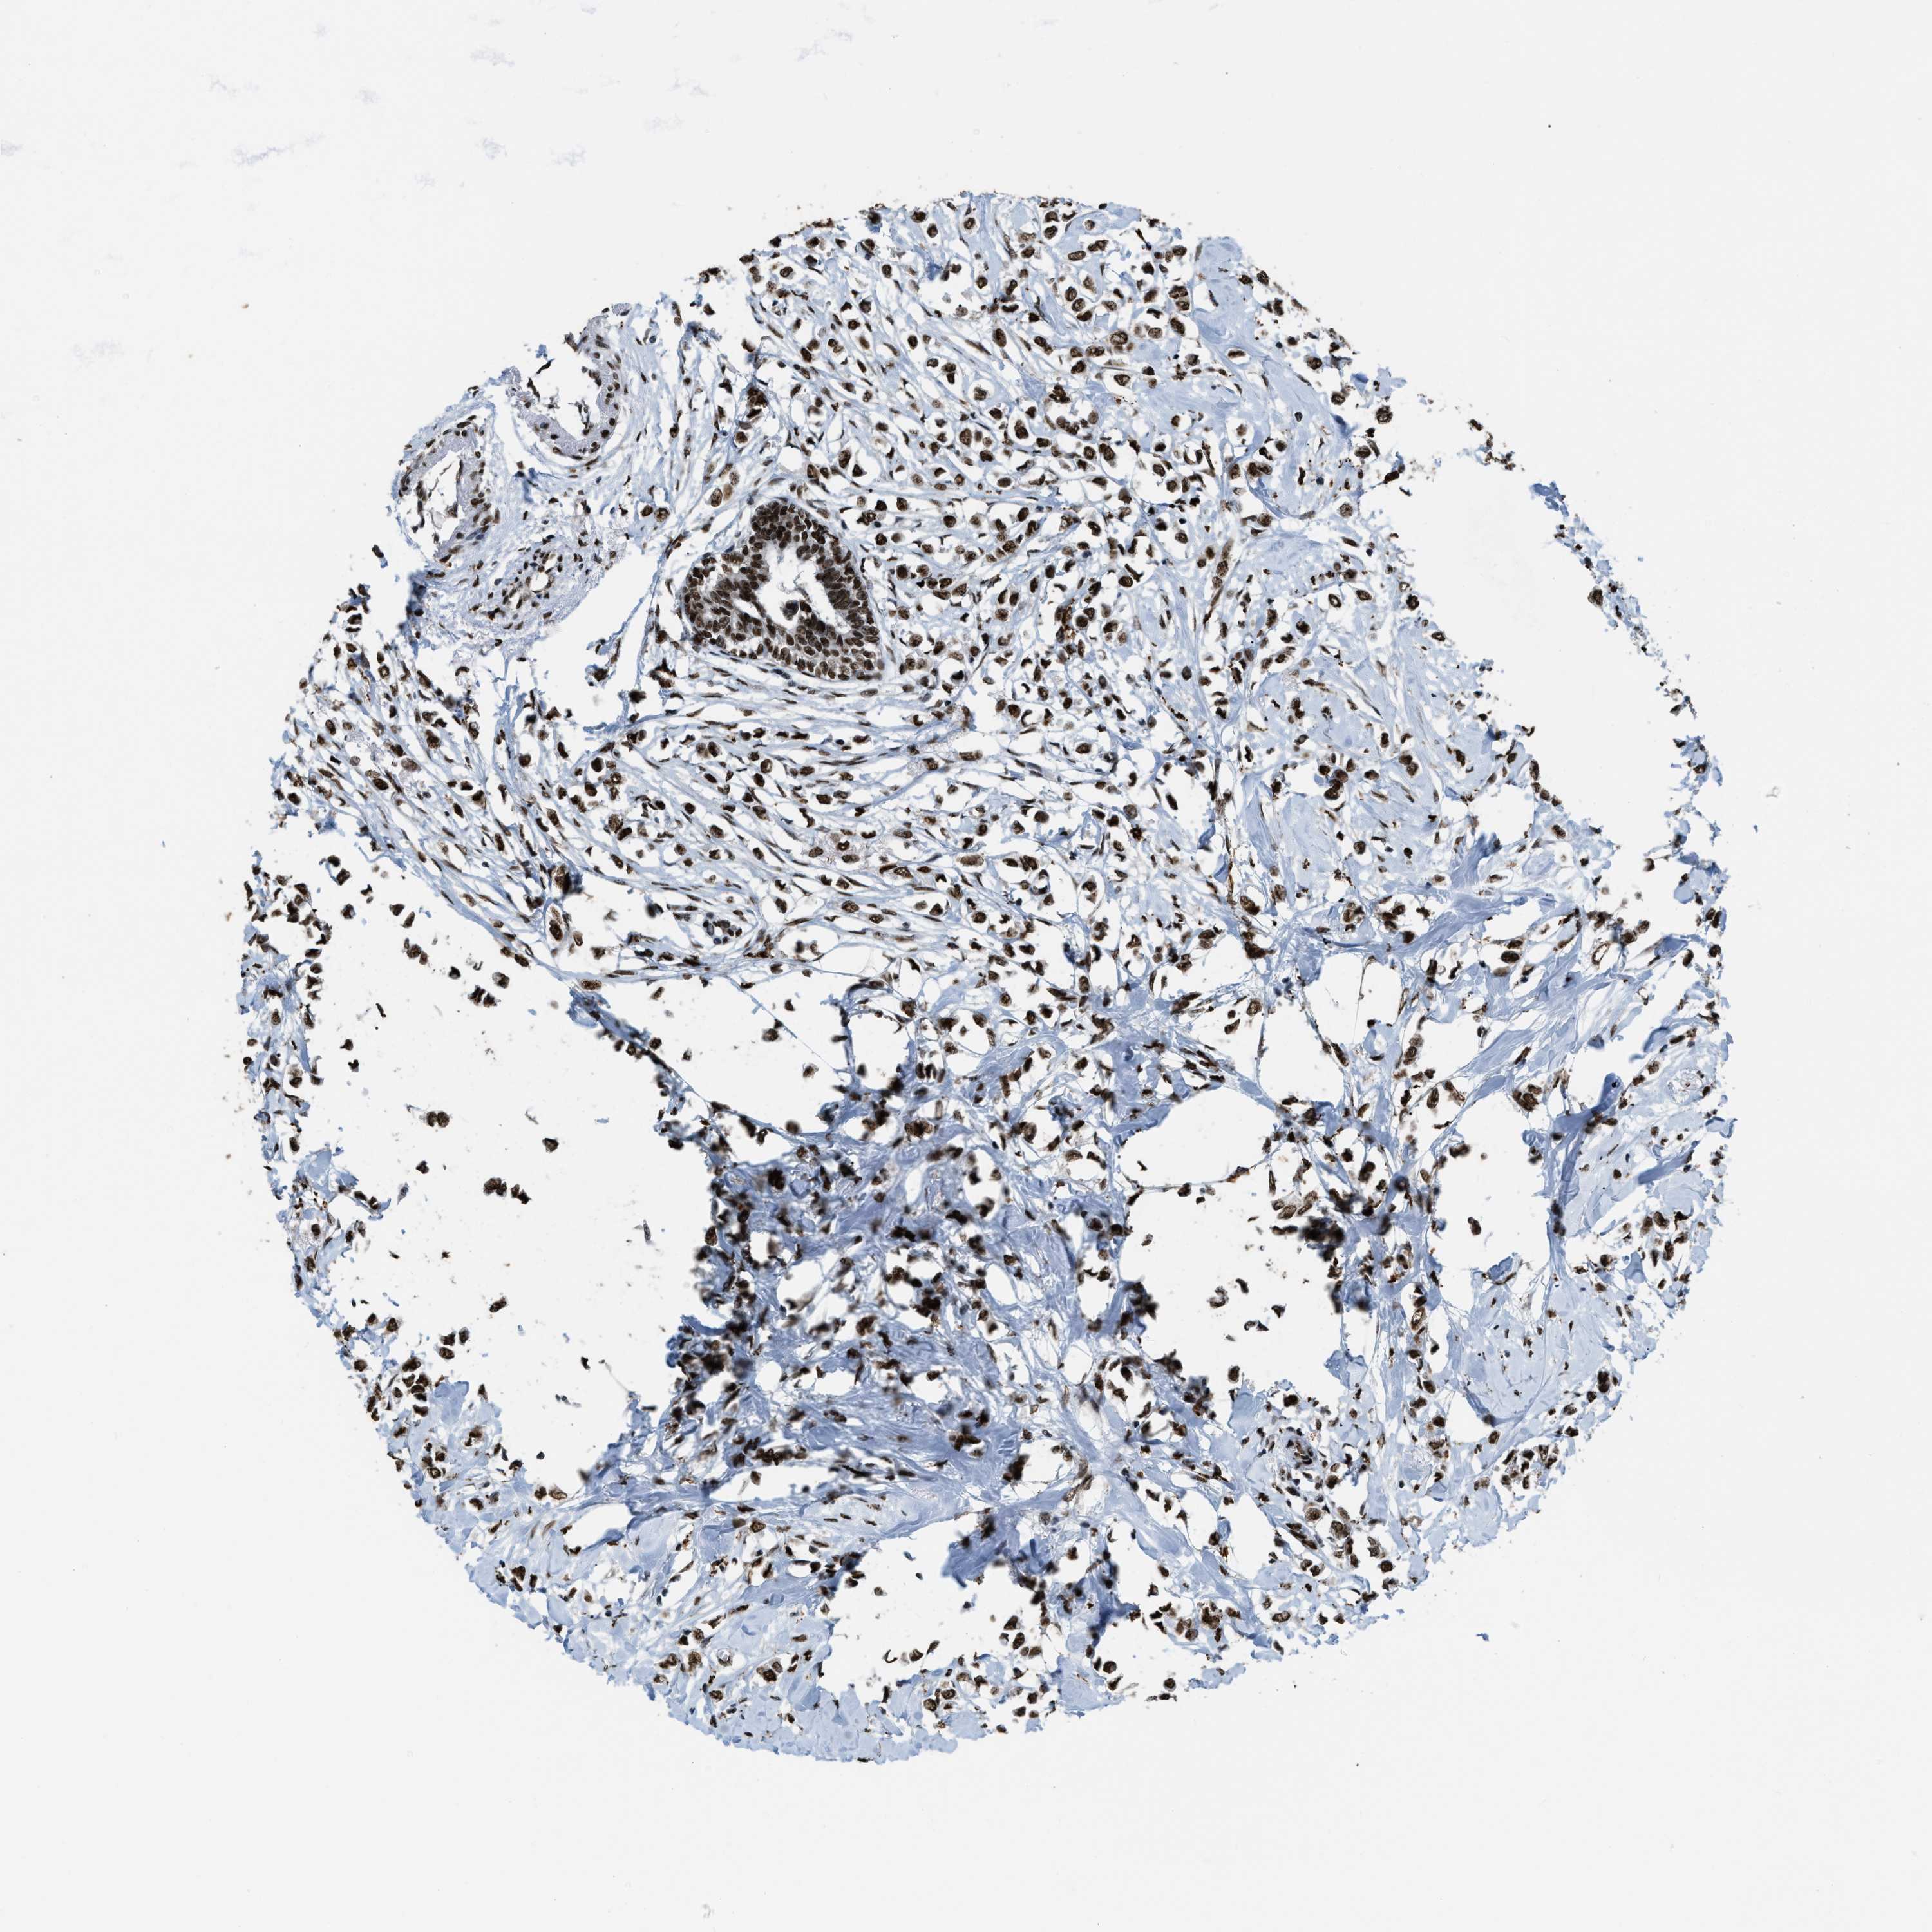

BRCA TCGA BRCA VALIDATION PROTEIN EXPRESSION

ANTIBODIES

AND

VALIDATION